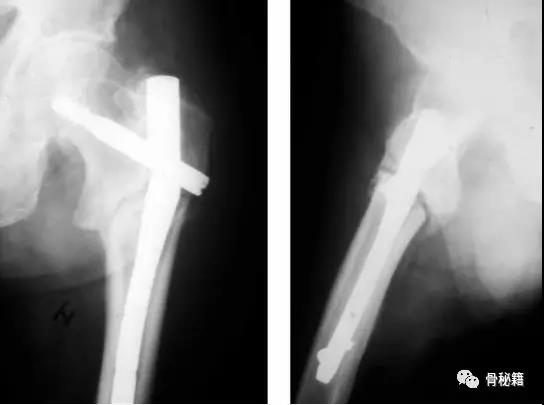

来一个比较有意思的病例大家讨论:

一个双膦酸盐治疗5年的患者粗隆下非典型骨折

采用了髓内钉固定,术后一年内固定失效

更换了DCS+植骨固定,术后四个月又发现了内固定失效再次更换了更长的DCS

这次的固定能成功吗?